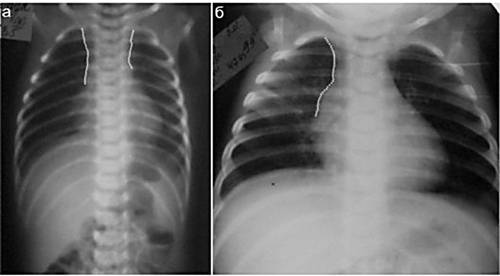

Нарушения в работе вилочковой железы в раннем возрасте ведут к потере сопротивляемости бактериям и вирусам. Такой ребенок постоянно болеет, подвержен вирусным инфекциям. Защитные функции организма снижаются при увеличении вилочковой железы. Поставить такой диагноз можно, сделав рентген грудной области. Увеличенная железа (см. прил. 3) выглядит темным пятном на фоне легких. При серьезных поражениях железы ее удаляют. Но чаще врачи советуют укреплять иммунитет медикаментозным способом.

Из инструментальных методов, позволяющих объективно выявить тимомегалию, используются рентгенодиагностика и ультразвуковое исследование (УЗИ).

Увеличение тимуса